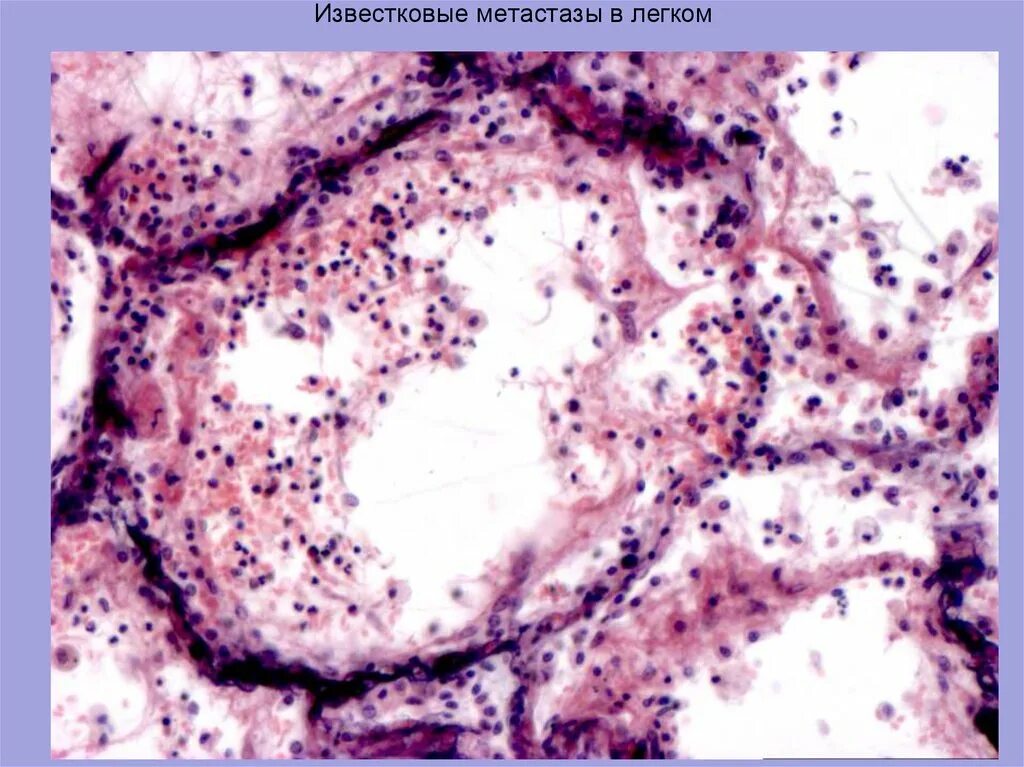

Что такое метастазы простыми словами